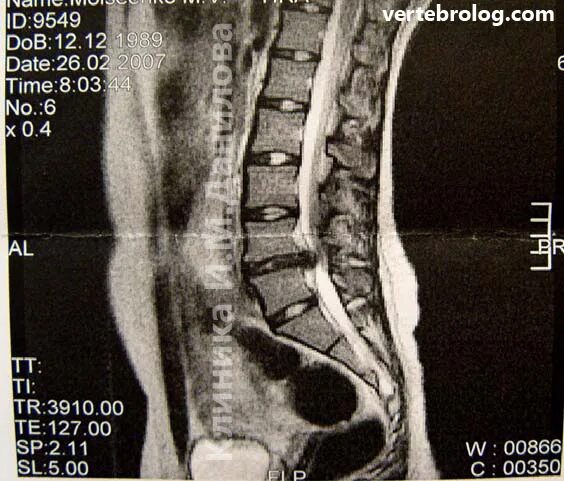

Грыжа 4 5